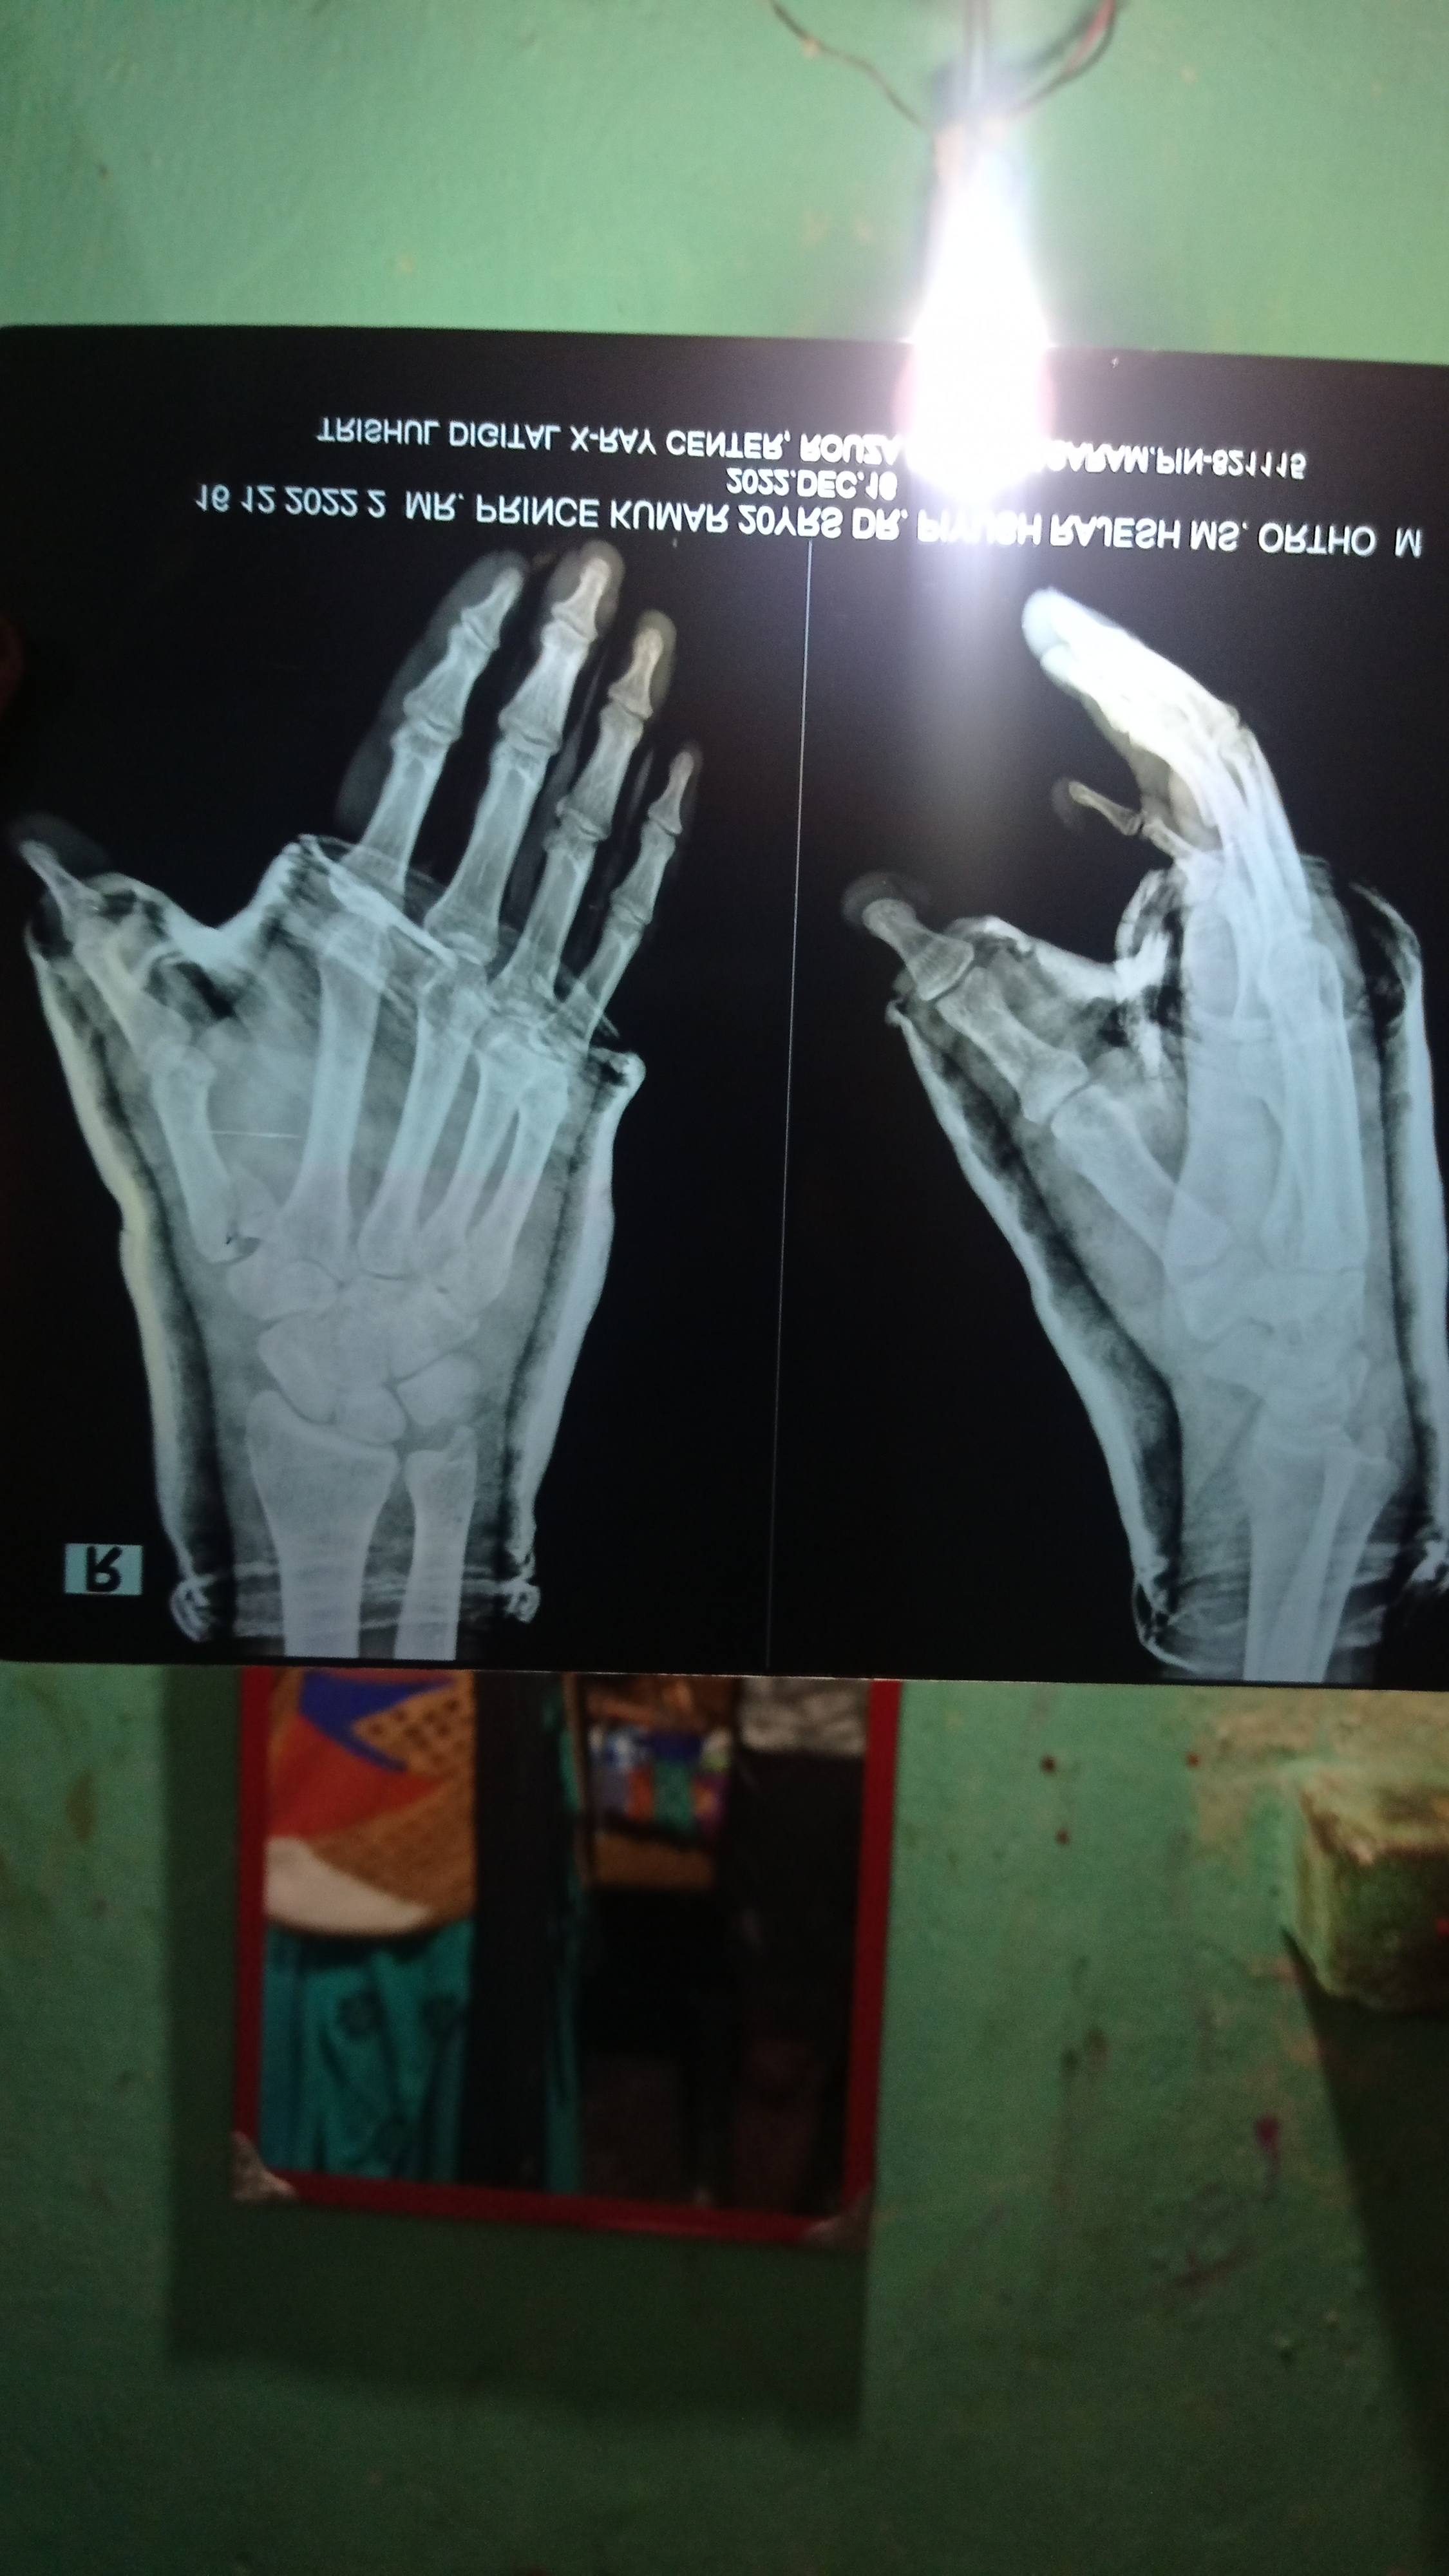

prince kumar